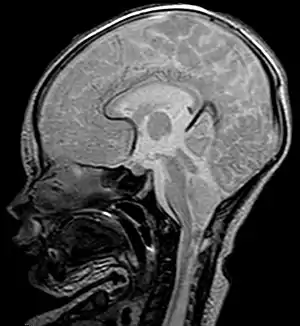

![]() Imagen radiográfica de una persona con malformación de Chiari tipo I. Una parte del cerebelo (amígdala cerebelosa), ha descendido 7 mm por debajo del foramen magno (agujero occipital). | ||

Si las amígdalas cerebelosas son empujadas al canal medular sin involucrar al tallo cerebral, se considera que la Chiari es del tipo I. Afortunadamente,[7] ya que es el tipo más frecuente. Normalmente solo se diagnostica en la adultez, durante un examen dirigido a diagnosticar otras patologías. Todas las Chiari adquiridas o secundarias pertenecen exclusivamente al tipo I.[7]

- Resonancia magnética, también llamada RM o IRM. Manifiesta al 100% tipo y grado de Chiari.